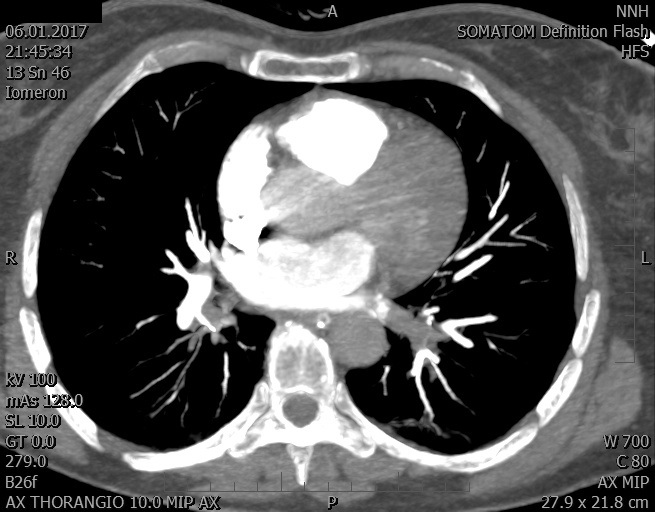

Video 2 - Echokardiograficky byla zjištěna těžká dysfunkce dilatační levé komory s nezvětšenou pravou komorou.Pro nejasnou příčinu zástavy jsme provedli i vyšetření výpočetní tomografií (CT), které vyloučilo plicní embolizaci (série 1 - soubory na konci článku). V den přijetí při přetrvávající oběhové nestabilitě byla nemocná opakovaně defibrilována pro fibrilaci komor se stabilizací rytmu po podání amiodaronu a mesocainu. Dle hemodynamických měření se jednalo o těžký kombinovaný šok. Vstupní laboratorní vyšetření bylo bez větších pozoruhodností. Posléze jsme doplnili anamnézu od příbuzných a zjistili, že pacientka užila do dvou hodin před srdeční zástavou první tabletu amoxicilinu na lehký respirační infekt. Při nevýtěžnosti vstupních vyšetření a nových anamnestických informacích jsme doplnili 14 hodin po kolapsu vyšetření koncentrace tryptázy v séru, která byla extrémně zvýšena (tabulka 2), což nás vedlo k podezření na anafylaxi.